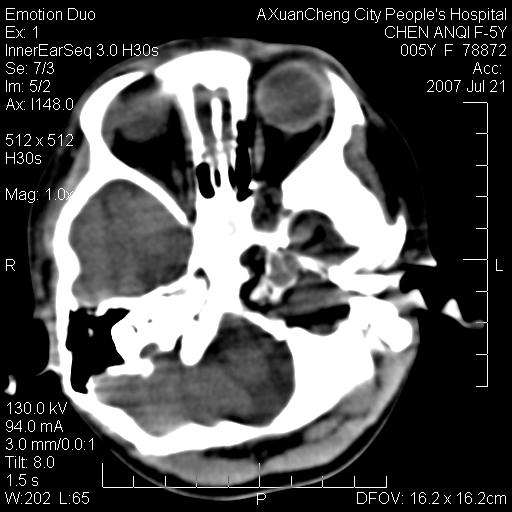

患儿5岁,左耳流脓痛疼一周,左外耳道肉芽组织填塞 软组织窗显示病灶内结节状低密度影为气体密度

考虑中耳乳突炎并胆脂瘤形成可能。

左侧中耳炎并胆脂瘤,左颞骨岩部骨质破坏并颅内感染积气。